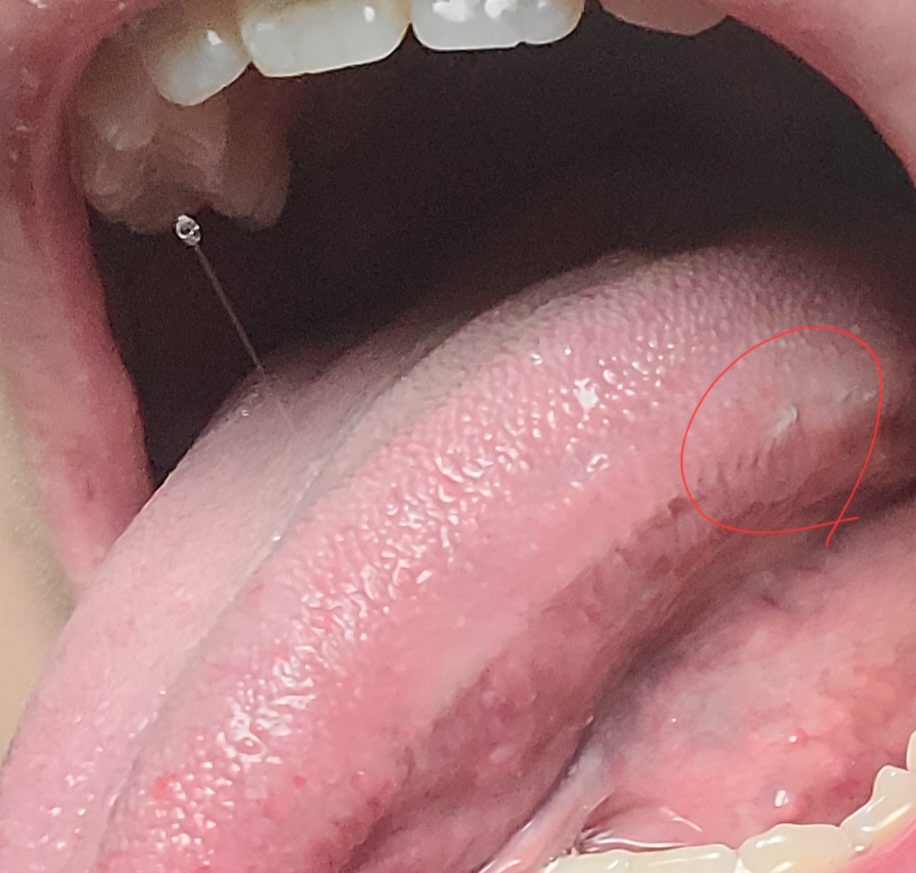

백반증이라고 일컫는 leukoplakia는 현재와 같은 양상이 아닙니다. 해당 부위는 치아로 인하여 씹힌 부위일 수 있습니다. 또한 자극에 의해 생긴 일시적인 구강 연조직 질환일 수 있습니다. 대부분은 2주 안에 사라지지만 2주가 지나도 있다면 치과 방문 후 감별진단을 받아봐야 합니다.

혀가 치아에 씹혀서 생긴것같습니다. 크게 문제가 잇는건 아니니 걱정은 안하셔도 될것같습니다.

백태를 무리해서 제거하면 상처가 날수있고, 돌기가 자라 더 많이 생길수 있습니다..백반증은 구강내에 하얀반점이 생기는 질환입니다.